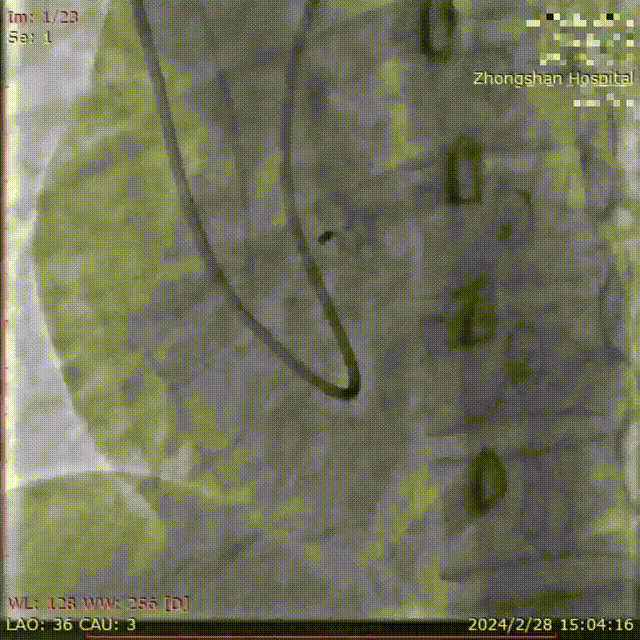

葛均波院士为患者植入FreeFlow经皮房间隔分流器,在DSA的监测下分流器左盘通过输送鞘管到达左心房并释放;回撤输送鞘管,释放分流器右盘;行牵拉试验,观察分流器形态、位置、左右心房分流情况;旋转输送钢缆将分流器完全释放;撤离输送钢缆、输送鞘管,手术圆满完成,分流器释放性能、输送系统操作性能均表现良好。复查心超/DSA,分流器位置、大小、形态合适,对周围结构无影响,清晰可见右向左分流。

术后分流器形态